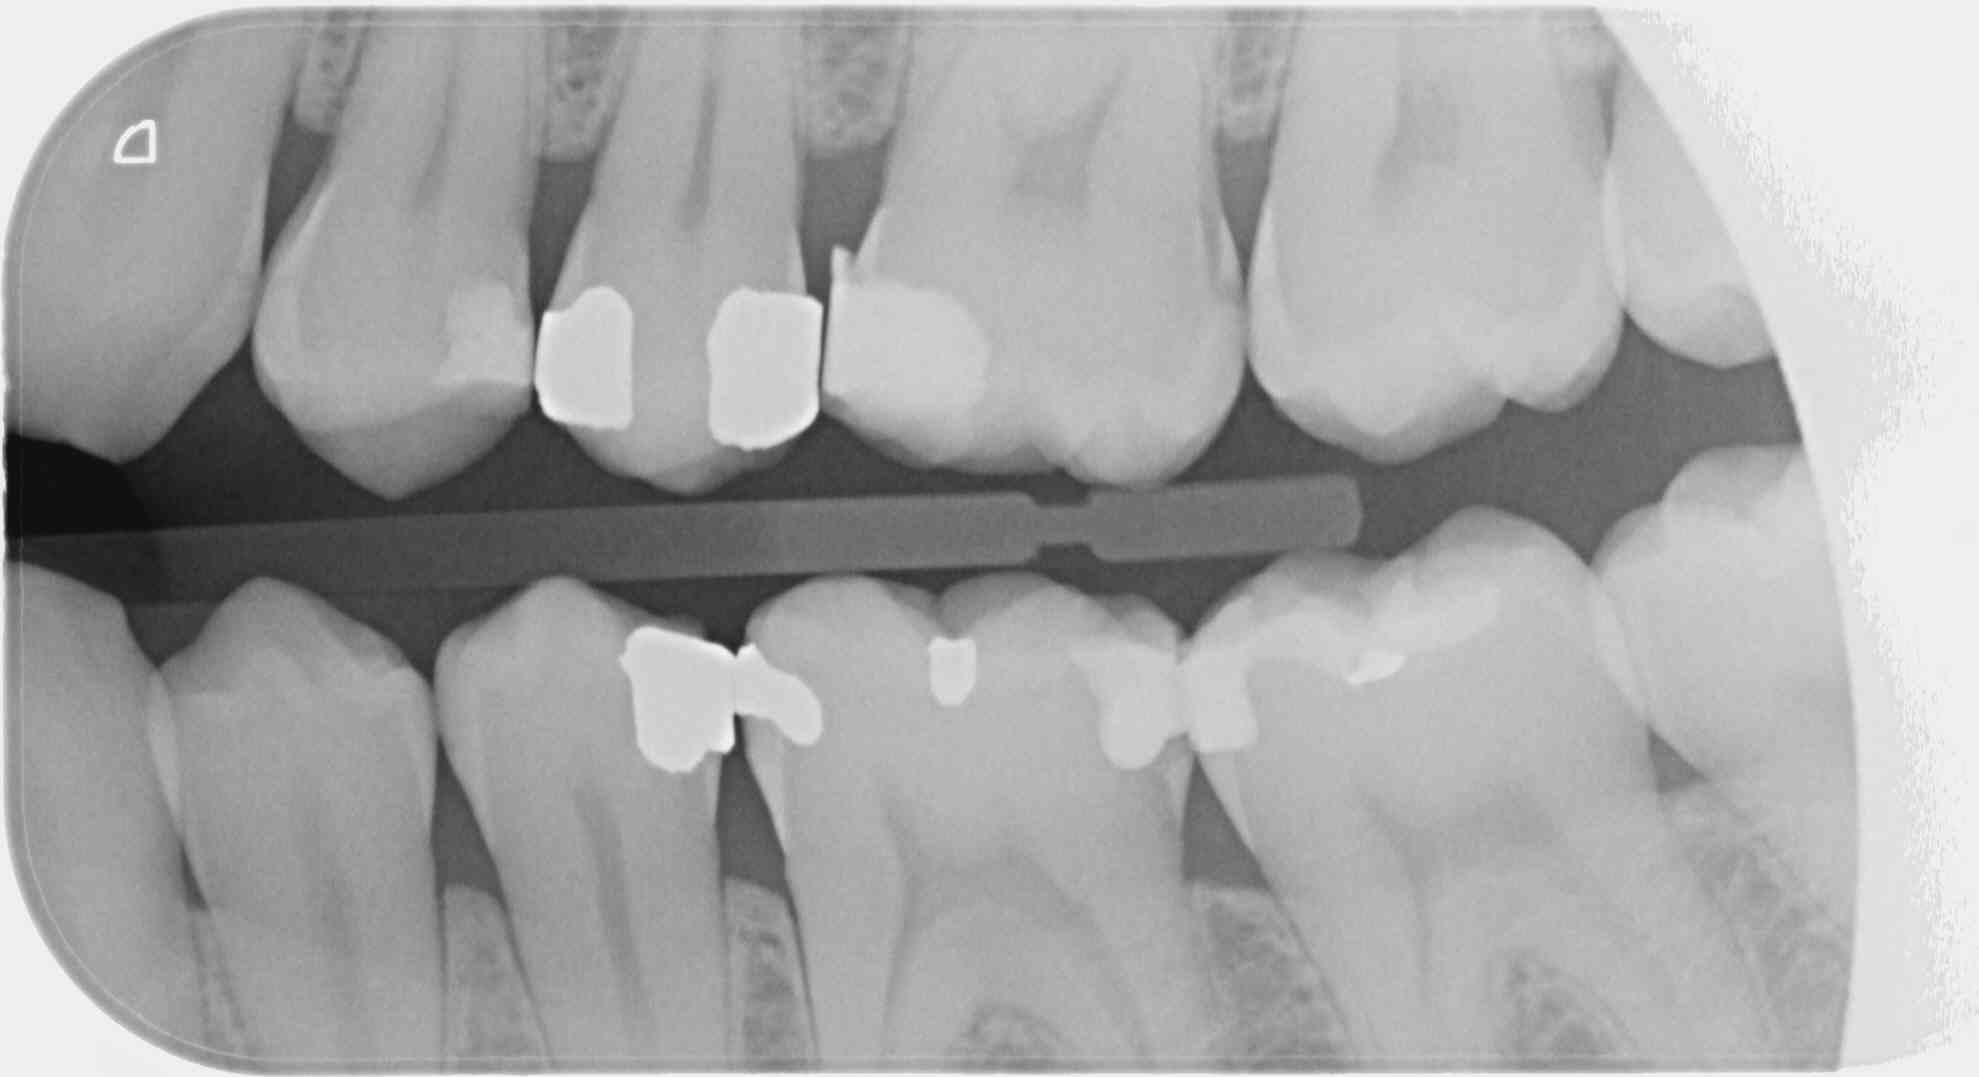

Tu fais une rétro coronaire centrée sur 16 donc 2 secteurs coté un seul. Si tu fais en plus une rétro alvéolaire centrée sur 46 dévitalisée est elle aussi gratuite ?

Un secteur est défini par la dent au centre du cliché. Pour une rétro coronaire 2 secteurs sauf si elle est seule. -))))

C'est une faille de la CCAM qui permet, avec un peu de mauvaise foi, de coder 4 secteurs avec seulement 2 clichés, le nombre de clichés n'étant pas précisé dans le libellé.

1 radio (au singulier) en bite-wing secteur 1 et 4 = 7.98€ (HBQK389, 2 secteurs mais 1 seul cliché)

2 radioS (au pluriel) en bite-wing secteurs 1, 2 , 3 et 4 = 31.92€ (HBQK443, 4 secteurs, plusieurs clichés sans précision sur leur nombre).

T'es con d'utiliser des films taille 3 surtout avec des CDC de bonne composition. ca fait que 2 secteurs ou 4. Alors que 4 clichés ca fait 4 secteurs....ou 8. Les rétro alvéolaires sont offertes. -)

Le problème vois tu avec ces films étendus c'est que moins tu as de clichés moins tu as de dents au centre d'un cliché et moins tu as de secteurs. -)))